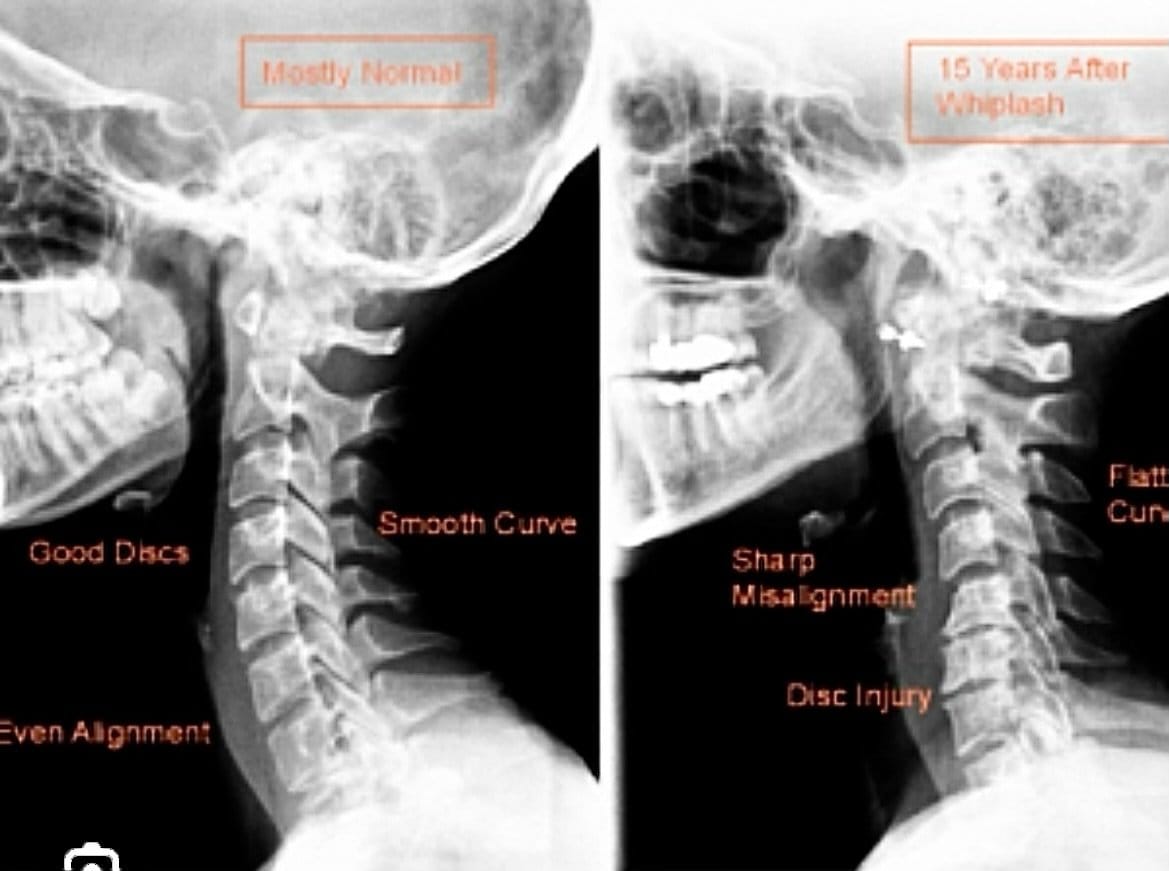

80% of car accident injuries cause whiplash trauma to the spine

This X-ray demonstrates the effects of a whiplash injury to the neck. Notice the difference in the curves. The left is normal, the right is really bad.